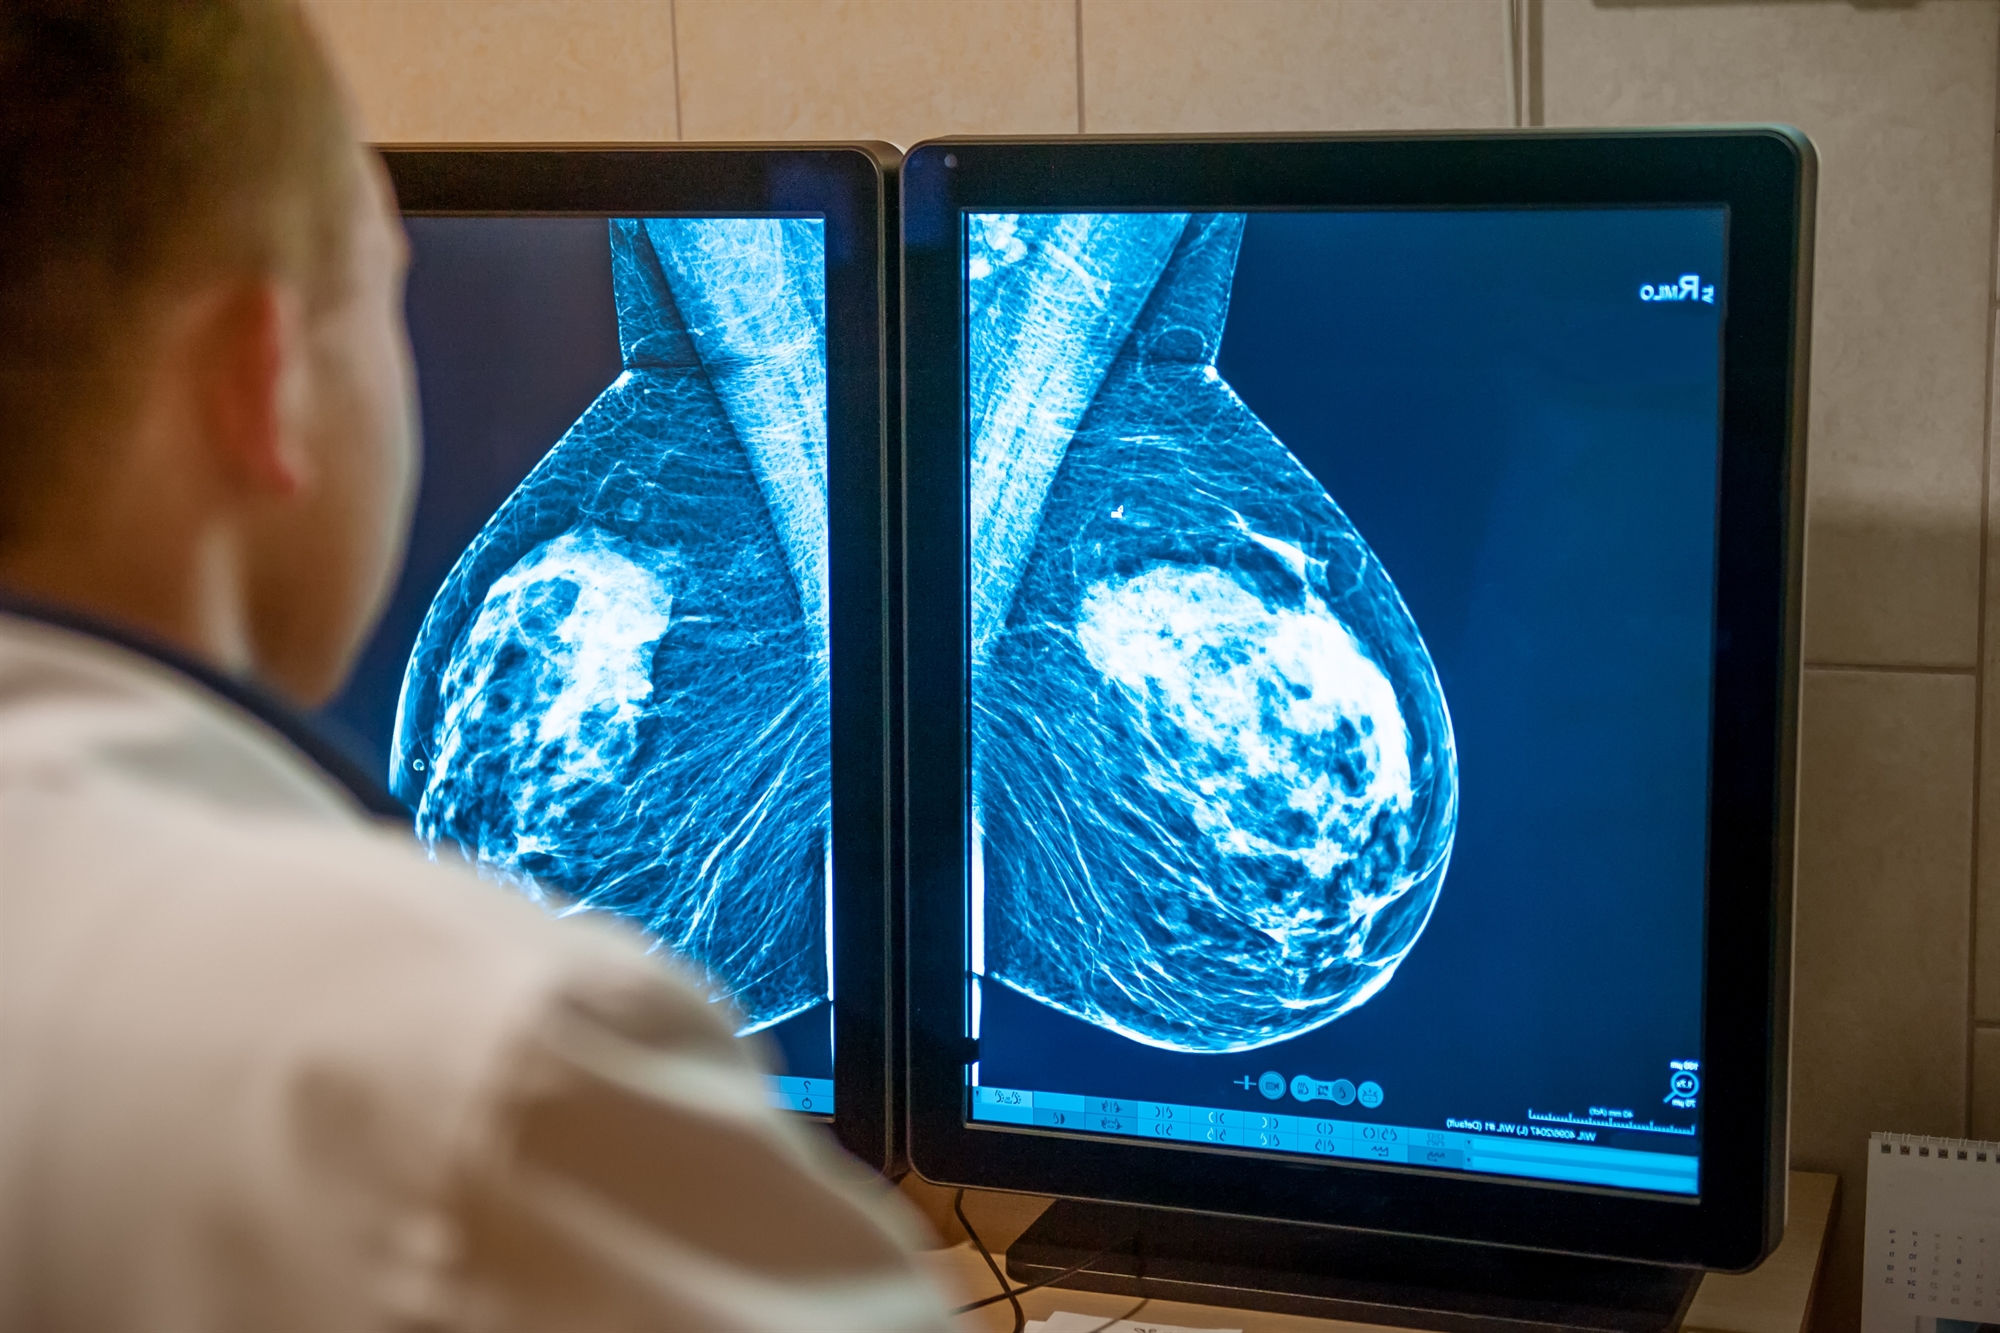

Η ψηφιακή μαστογραφία μάς δίνει απεικονίσεις του μαστού υπό διαφορετικές γωνίες με χρήση χαμηλής δόσης ακτίνων Χ. Στις απεικονίσεις που προκύπτουν, οι περιοχές που εμφανίζονται λευκές αντιπροσωπεύουν αδενικό ιστό και οι μαύρες περιοχές απεικονίζουν το λίπος. Παρότι η μαστογραφία έχει υψηλή αποτελεσματικότητα στην ανίχνευση καρκίνου του μαστού, οι εικόνες μπορεί να είναι δυσκολότερο να διαβαστούν σε γυναίκες με πυκνούς μαστούς διότι ο καρκίνος εμφανίζεται με τη μορφή λευκών περιοχών, ακριβώς όπως ο πυκνός μαστικός ιστός.

«Αυτό που προσπαθούμε να δούμε είναι ένας λευκός όγκος κρυμμένος σε λευκό αδενικό ιστό», εξηγεί η δρ Dialani. «Όσο περισσότερο πυκνό ιστό βλέπουμε, τόσο λιγότερες είναι οι πιθανότητες να κατορθώσουμε να δούμε έναν όγκο που κρύβεται εκεί». Άλλες απεικονιστικές εξετάσεις, όμως, μπορούν να βοηθήσουν στην ανίχνευση καρκίνων που ενδεχομένως να διέφευγαν της προσοχής αν χρησιμοποιούσαμε αποκλειστικά μαστογραφία.